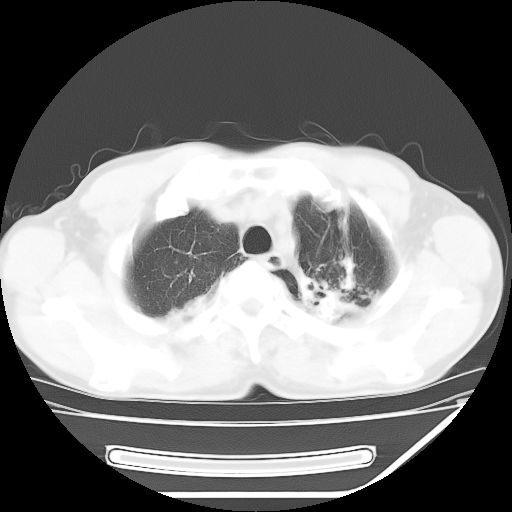

男,59岁,“结核性胸膜炎”30余年,胸部经常疼痛,多次x检查提示“肺部”炎症。腹部疼痛5日,b超提示:“肝内短管结石,余显示不清,建议进一步检查。”

两肺结核并右侧胸腔积液;脾脏、腹腔及腹膜后淋巴结结核[陈旧性];肝内胆管结石

胸部腹部都是结核(双肺。纵隔淋巴结,肝脏,脾脏,肠系膜)

结核,是血行播散还是淋巴?